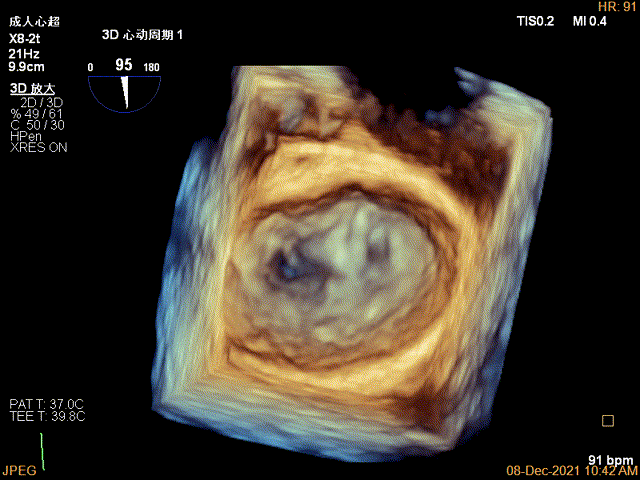

3D视图下调整夹子位置及Rotate

3D-VIEW验证结果